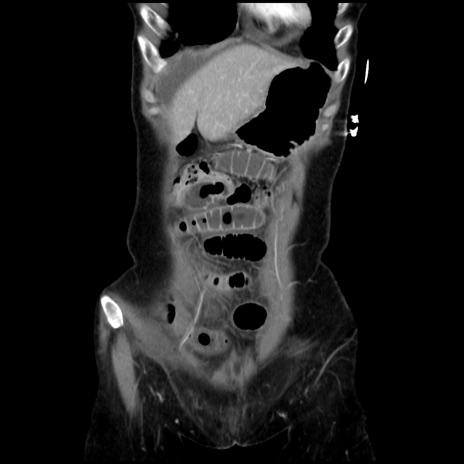

矢状断像

【症例】40歳代 女性

【主訴】上腹部痛、嘔気・嘔吐

【現病歴】約9時間前頃から急に上腹部痛、嘔気、嘔吐が出現。改善しないため救急要請。

【既往歴】子宮頚癌(広汎子宮全摘術、放射線療法)、腸閉塞

【身体所見】腹部:平坦、軟、腸雑音亢進、上腹部を中心に腹部全体に圧痛あり。

【データ】WBC 8400、CRP 0.03